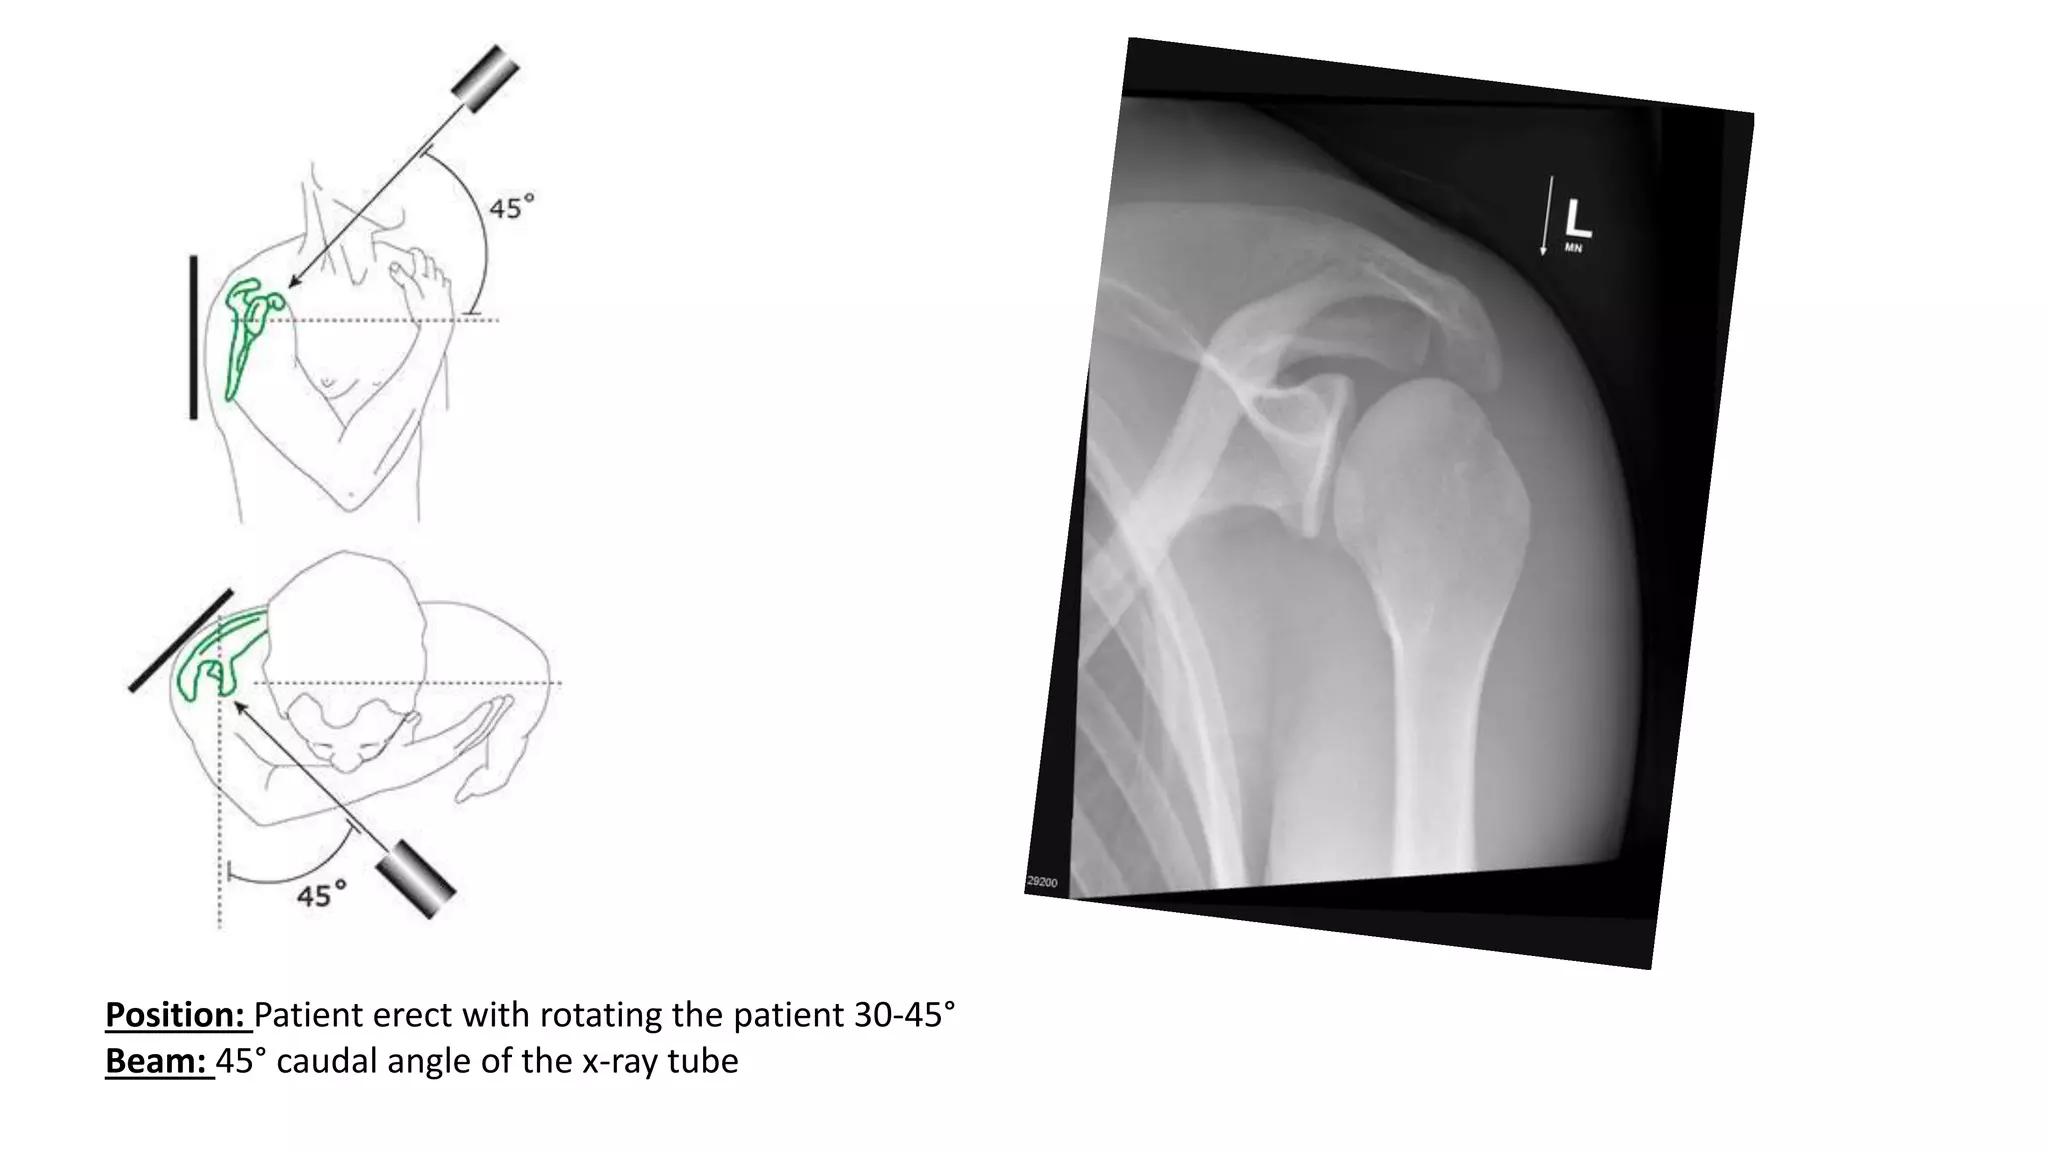

6. GARTH APICAL OBLIQUE VIEW

Position: Patient erect with rotating the patient 30-45°

Beam: 45° caudal angle of the x-ray tube

6. GARTH APICALOBLIQUE VIEW • The Garth view of the shoulder is a projection used in trauma when evaluating the glenohumeral joint for dislocations and trauma to the glenoid of the scapula. • It shows antero inferior glenoid rim. • This projection is often used as a replacement to the lateral scapula view in trauma. • It is an optimal projection to demonstrate Bankart and Hill-Sachs lesions

Position: Patient erectwith rotating the patient 30-45° Beam: 45° caudal angle of the x-ray tube